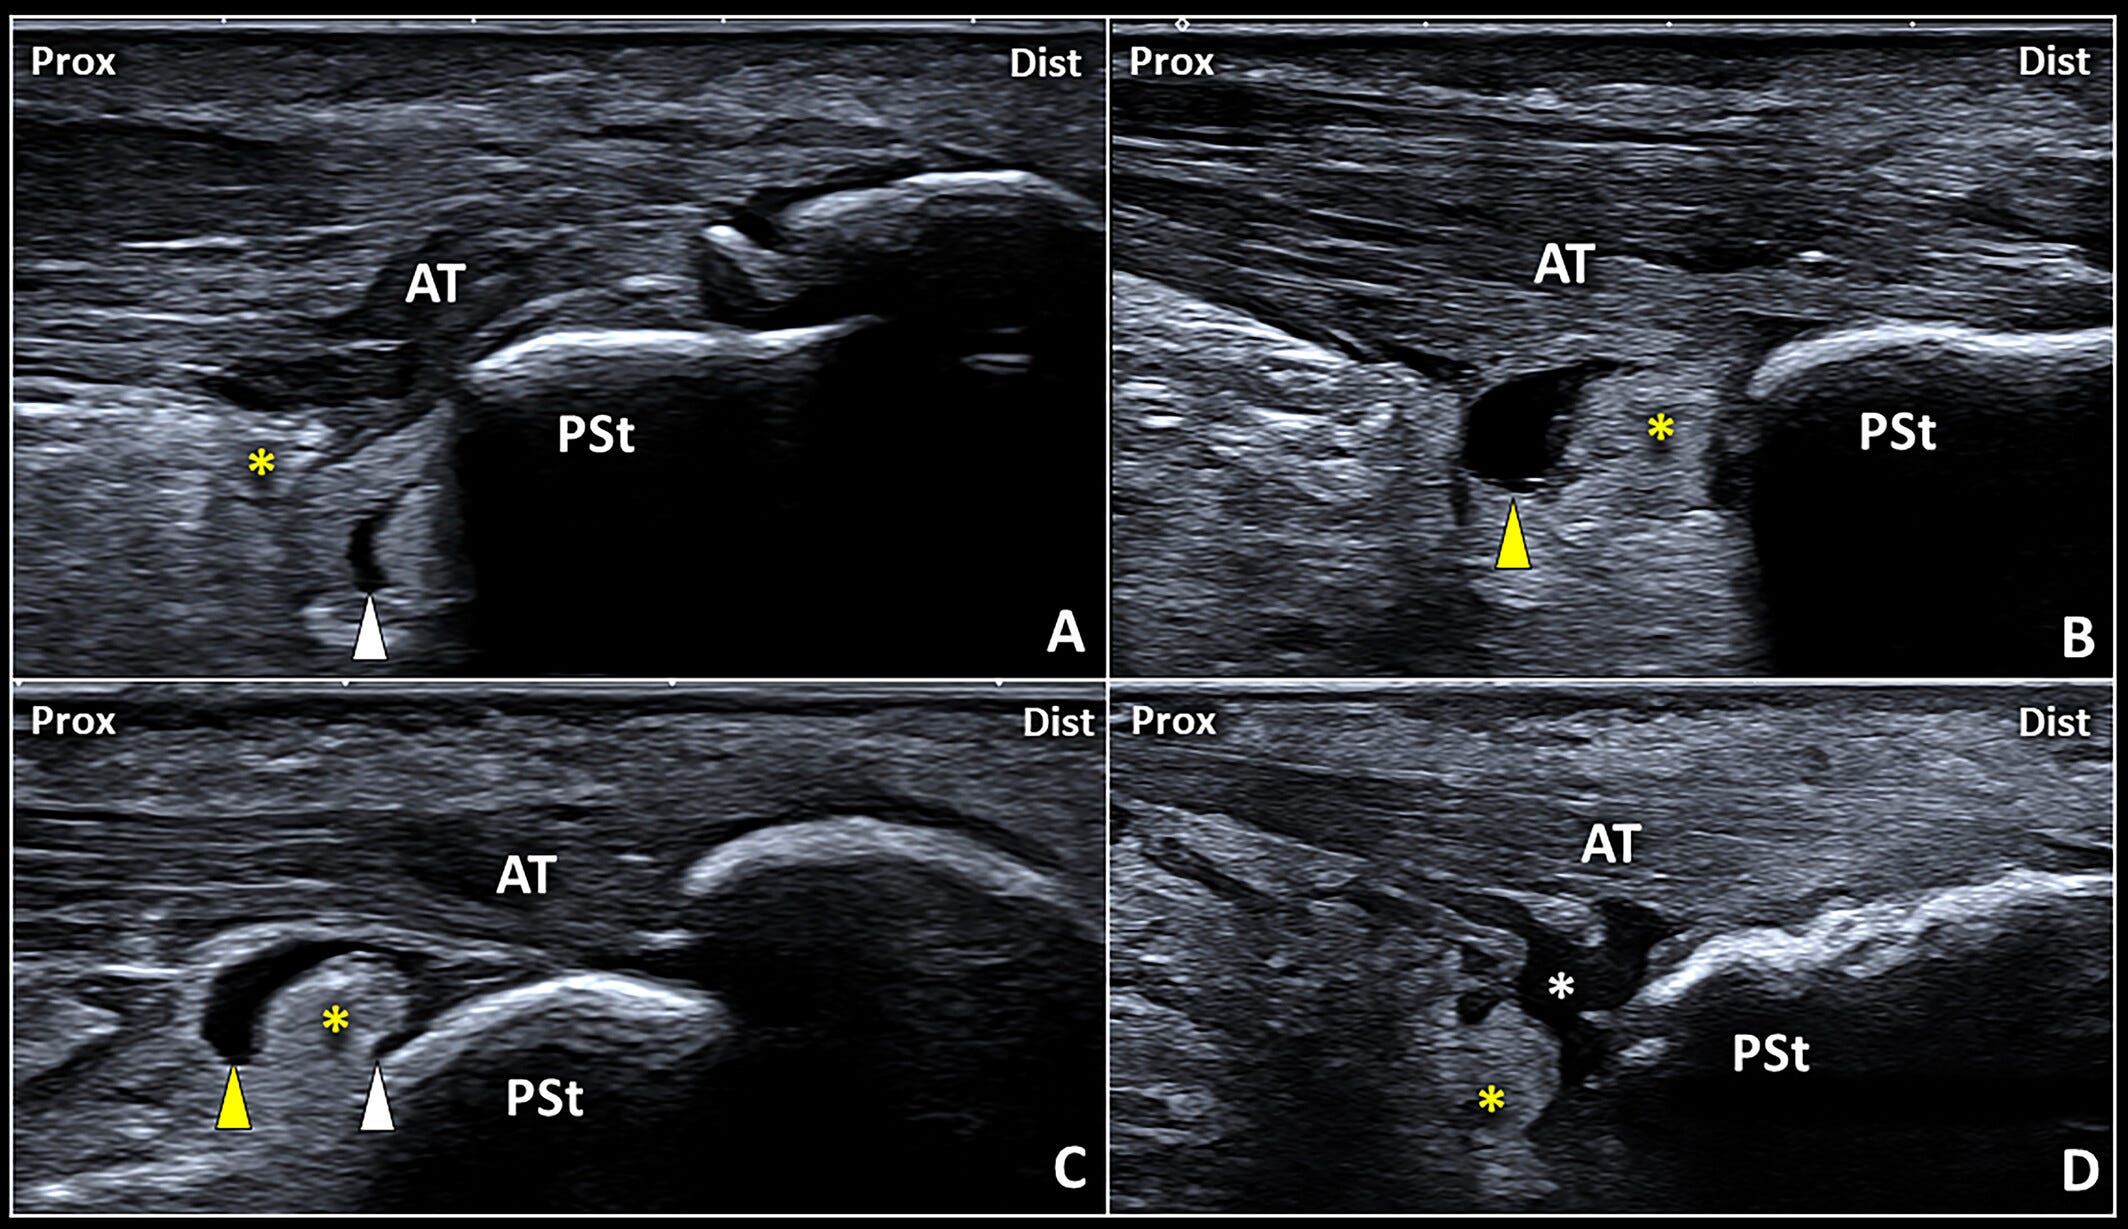

Patrones ecográficos del derrame de la bursa retrocalcánea.

La distensión en forma de coma del receso anterior (punta de flecha blanca) (A), la dilatación del receso posterior (punta de flecha amarilla) (B) y la afectación simultánea de los recesos anterior y posterior en forma de U invertida (C) pueden considerarse los tres patrones ecográficos más frecuentes del derrame bursátil.

Con menor frecuencia, puede identificarse una bursa retrocalcánea (RCB) de morfología irregular, con múltiples digitaciones periféricas de la sinovial (asterisco blanco), en pacientes con tendinopatía aquílea insercional (IAT) (D).

AT: tendón de Aquiles; Dist: distal; Prox: proximal;

PSt: tuberosidad posterosuperior del calcáneo;

asterisco amarillo: cuña posteroinferior (PIW) de la almohadilla grasa de Kager.

Dependiendo de dónde se localice el líquido y cuánto se acumule, se pueden observar distintos patrones ecográficos. Por ejemplo, en una pequeña cantidad de derrame, localizada en el receso anterior de la bursa, la imagen adquiere una forma de coma entre la tuberosidad posterosuperior del calcáneo (PSTC) y la grasa de Kager. En cambio, si el líquido distiende el receso posterior, la bursa adopta una forma de globo, comprimiendo mecánicamente la grasa contra el hueso.

Cuando el líquido ocupa tanto el receso anterior como el posterior, la forma ecográfica de la bursa cambia de nuevo, mostrando una “U” invertida, con la grasa interpuesta entre ambas expansiones sinoviales. En otros casos, menos comunes pero igualmente relevantes, la bursa puede presentar contornos irregulares con digitaciones periféricas, consecuencia de una sinovial más activa o irritada.